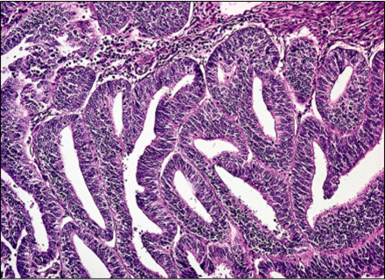

Diagnóstico e micro. Hiperplasia Endometrial Complexa de Baixo Grau. Glândulas proliferadas, tortuosas, irregulares e justapostas sem atipias.

Hiperplasia Endometrial Complexa de Alto Grau.

Descreva os estágios de classificação do adenocarcinoma de endométrio. Grau I - Predomínio de Glândulas (bem diferenciado). Grau II - Glândulas em proporção semelhante à área sólida (moderadamente diferenciado). Grau III - Há predomínio de áreas sólidas (cels epiteliais proliferadas), (pouco diferenciado).

Adenocarcinoma de Endométrio Grau I.

Adenocarcinoma de Endométrio Grau II.

Adenocarcinoma de endométrio grau III.